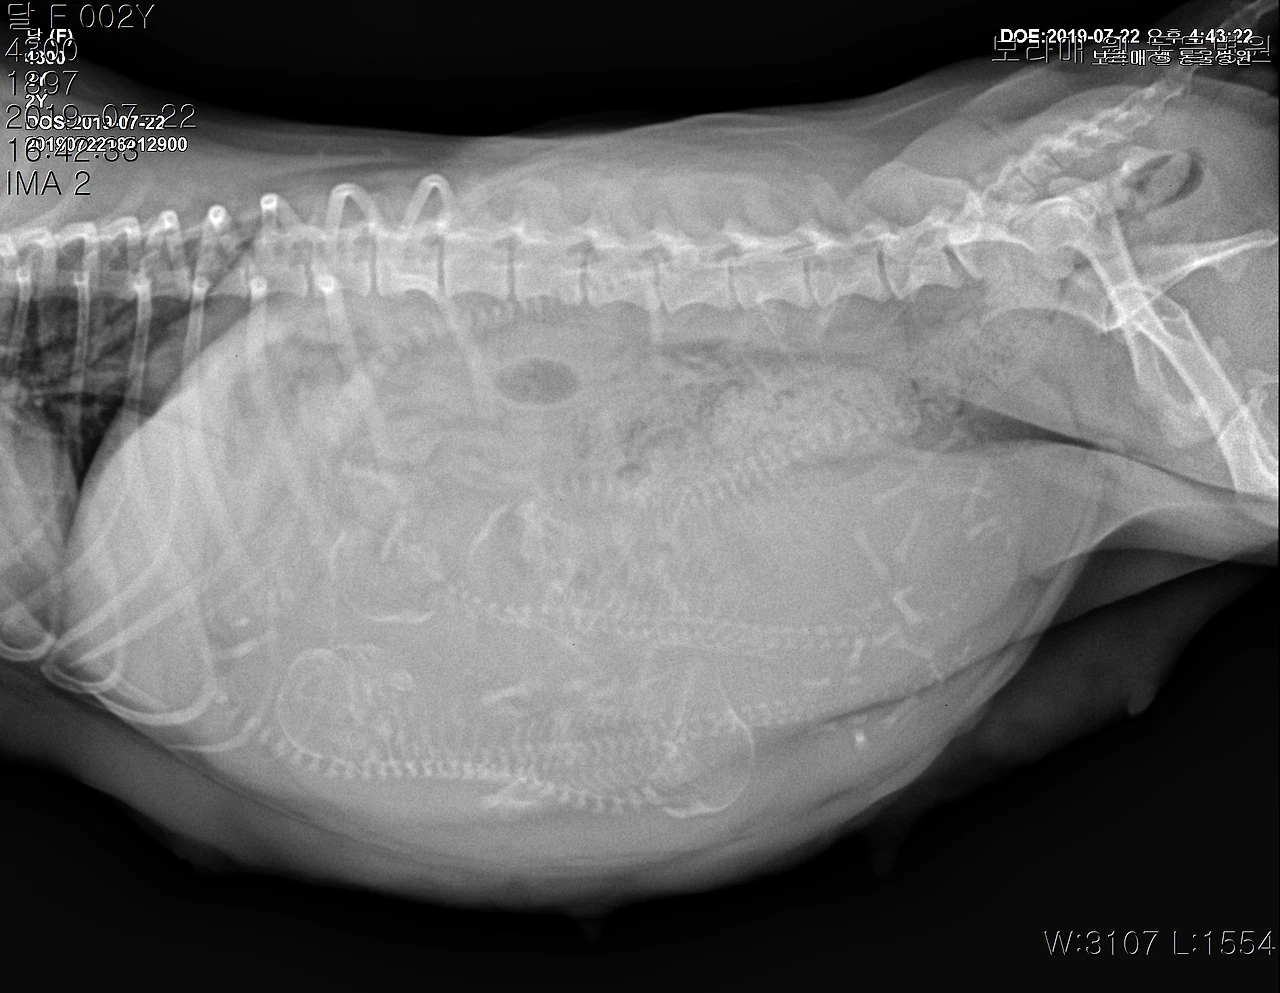

그러던 두 개가 3년 만에 교배에 성공했다. 두 달 전 얘기다. 현장을 목격한 우리는 당황했지만 어쩔 줄 몰라 일단 내버려 두고 네이버 지식을 검색했다. 분명히 자연교배에 성공했으니 60~65일 후면 새끼가 나온다는 거였다. 헉.. 두 달 만에 새끼를?? 우리 가족은 모두 당황했지만 예쁜 새끼를 본다는 기대감에 부풀어 달이 배만 쳐다보며 한 달여를 기다렸다. 그런데 한 달이 조금 지나니 배가 진짜 불러오는 게 아닌가? 몸이 점점 무거워지고 배가 부풀더니 한 달 반이 되니 배가 바닥에 닿을 지경이다. 일단 50일경 엑스레이를 찍어보면 새끼가 몇 마리인지 확인이 된다고 해서 병원에 가보니 다섯마리가 꼬물거리고 있단다. 꺅!! 어떻게!! 진심 걱정반 기대반.. 어떻게 새끼를 낳을지 걱정과 안쓰러움이 밀려온다.